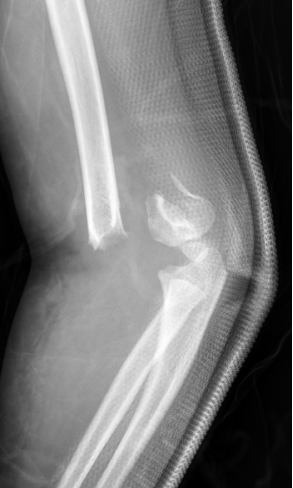

2、小雨(化名):女、8岁、在小区游乐场吊单杠时不慎摔伤致右肘部肿痛、畸形、活动受限1小时就诊我院。(下图为患儿术前X线片)

麻醉下手法整复经皮钢针内固定,术后患儿恢复良好。(下图为患儿术后X线片)